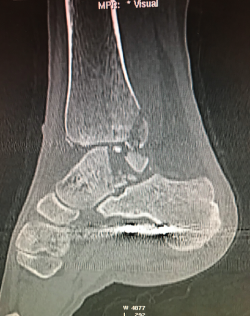

Figura 15. Control posquirúrgico tras la corrección de la pseudoartrosis en varo.

- Control posquirúrgico tras la corrección de la pseudoartrosis en varo (Figura 15).